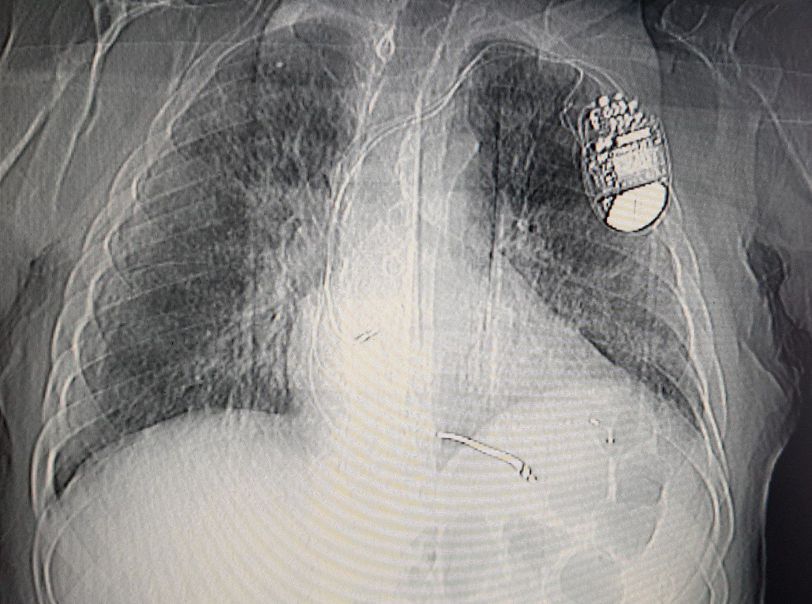

COVID-19 TORAX CT + PACEMAKER

Cardiology

Lungs

Covid 19